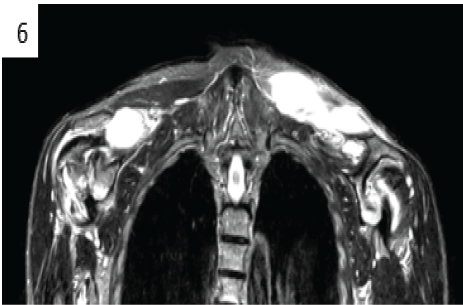

Mucoid Degeneration of Posterior Cruciate Ligament – A Case Study

Amit Kumar Jha , Ankit Chaubey , Swaroop Patel , Santosh Kumar Singh , Amit Singh ………………………………p.153-156